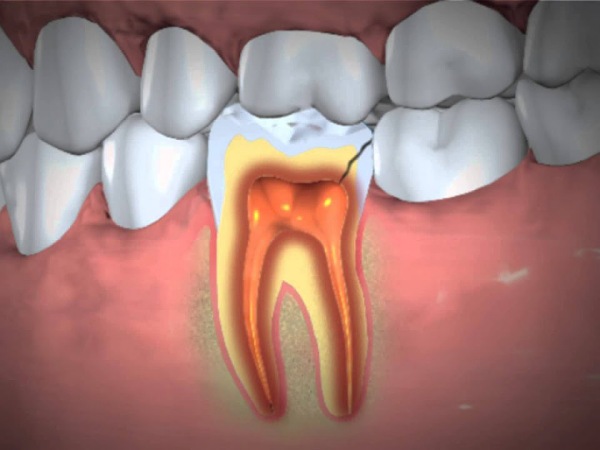

An abscessed tooth is a result of the soft tissue inside the root canal dies and becomes inflamed. The inflammation is caused by the bacteria that exist in plaque (a by-product of food, saliva, and bacteria), which damage and destroy the teeth and the gums.

Tooth abscess develops from the tooth's inner chamber (pulp chamber) because the tooth has essentially lost the ability to fight off the infection-causing bacteria; causing the bacteria to multiply and spread the infection. An abscessed tooth has to be treated or else can turn into life-threatening conditions, as the infection can spread to the jaw to your neck, head, or other body parts. An abscessed tooth can affect anyone, irrespective of age and gender [3] , [4] .

Root canal procedure: This procedure involves drilling into the affected tooth, so as to drain the abscess and to remove any infection. After that, the pulp chamber and the root canal will be filled and sealed. It will be followed up with a crown procedure, which is to put a cap on your teeth to strengthen the root canal procedure done.